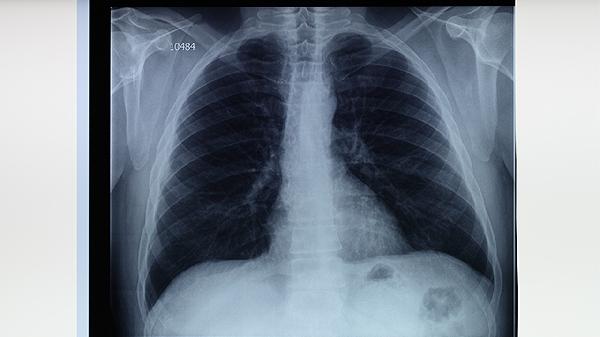

肺部或纵隔肿瘤可能压迫或侵犯肺动脉,导致血管壁受损并形成肺动脉瘘。肿瘤引起的肺动脉瘘可能伴随体重下降、乏力、咯血等症状,需通过影像学检查明确诊断。